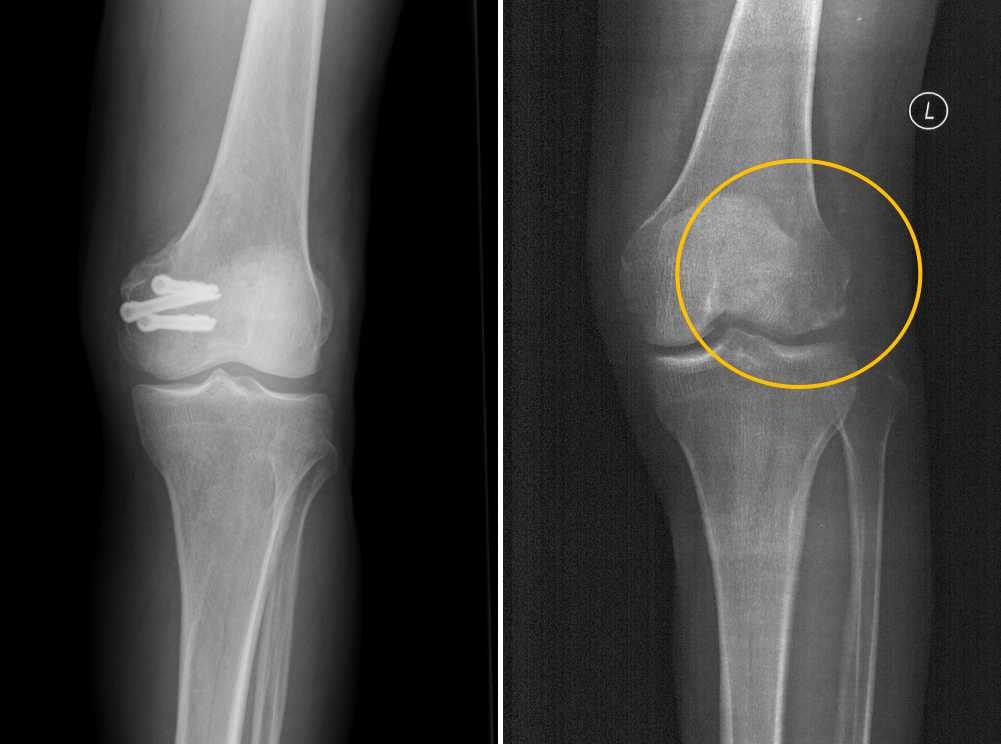

蚕丝螺钉外观 受访者供图

今年5月份,患者张强(化名),不慎扭伤,造成左股骨远端骨折。入驻西京医院后,医院骨科雷伟教授团队针对患者骨折部位靠近关节面,使用金属螺钉固定时应力过大,会影响骨折愈合,一年后还需要实施惯例手术再次取出,形成二次创伤的实际。经过反复论证细致阅片后决定,对其手术时使用本院骨科自主研发的可降解蚕丝螺钉固定。术后患者CT片中没有任何伪影,可以清晰地看到骨折块已经完全复位,解除了患者二次手术取出的负担和困扰。

术前(左)及术后(右)三维CT图像 受访者供图

患者张强已经是第五例在西京医院接受蚕丝接骨螺钉的患者了。据西京医院骨科冯亚非副教授告诉介绍,早在今年三月份,一名髋臼及股骨头骨折的患者在西京医院骨科接受了蚕丝螺钉固定手术,成功实现了世界首例可降解蚕丝骨钉的人体内应用。患者术后三个月复查时,已可以下地行走,无需借助护具保护。术后复查显示骨折已完全愈合,螺钉植入部位未发现明显的免疫排斥反应,体现出良好的生物相容性。我们与中科院上海微系统所陶虎研究员团队共同开发的这款可降解蚕丝螺钉植入人体内初期降解速度极为缓慢,以保证骨折坚强固定的需求;植入1年后螺钉逐渐酶解,降解产物为氨基酸和多肽,可完全被人体吸收,没有任何毒副作用。临床前研究证实,蚕丝螺钉在体内3年的降解率超过80%。